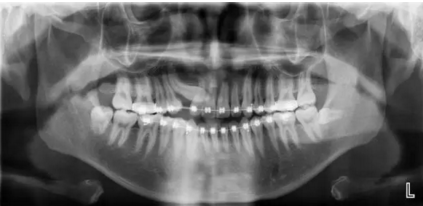

最近朋友圈轉(zhuǎn)發(fā)最多的一張片子,你知道嗎?

1.png